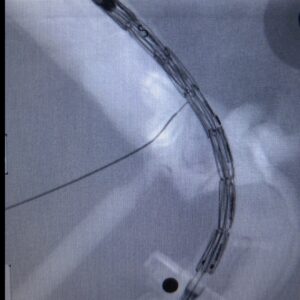

In this first case, the procedure initially involved the bench-top construction of the PMEG starting from a standard tubular endograft with a diameter of 26 mm. The PMEG was designed using a CT-guided model. Once modified, the endograft was implanted into the haptic model using an endovascular technique in the operating room at Niguarda, where it was possible to deploy the graft and cannulate the celiac, mesenteric, and renal arteries.

The entire PMEG simulation was completed in approximately 3.5 hours, from the beginning of the PMEG model design to the cannulation of the vessels. Timing was monitored to ensure the model could be replicated in emergency settings, enabling a time-effective decision-making process for both elective and urgent procedures.